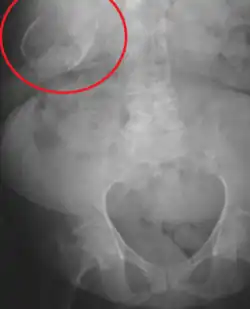

Porcelain gallbladder

| Porcelain gallbladder on X-ray | |

Porcelain gallbladder is a calcification of the gallbladder believed to be brought on by excessive gallstones, although the exact cause is not clear. As with gallstone disease in general, this condition occurs mostly in overweight female patients of middle age. It is a morphological variant of chronic cholecystitis. Inflammatory scarring of the wall, combined with dystrophic calcification within the wall transforms the gallbladder into a porcelain-like vessel. Removal of the gallbladder (cholecystectomy) is the recommended treatment.

Abdominal radiography (X-ray), abdominal ultrasound or CT scan.